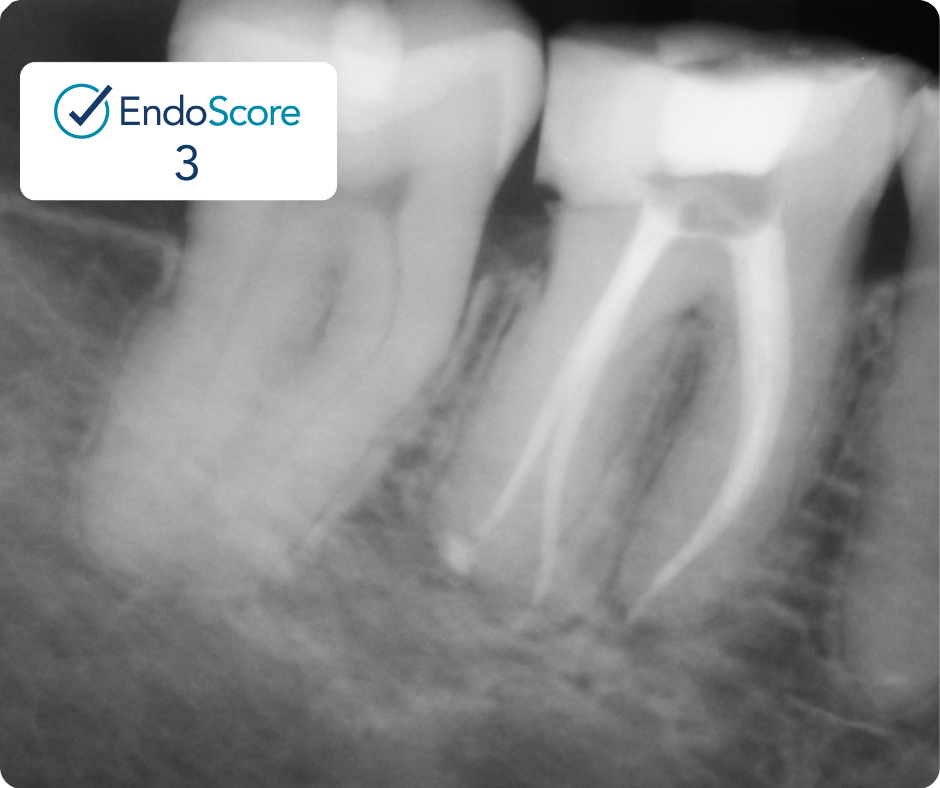

Case Study by Dr. Randy Cross

EndoScore of 3 at finish. Necrotic Symptomatic Apical Periodontitis. 2 visit with triple antibiotic paste, 30x06 conserve file with matching GP and Endoceramic sealer. Finished with bonded VistaApex clear flowable. The patient is being recalled in one year to confirm healing.

EndoScore: 3